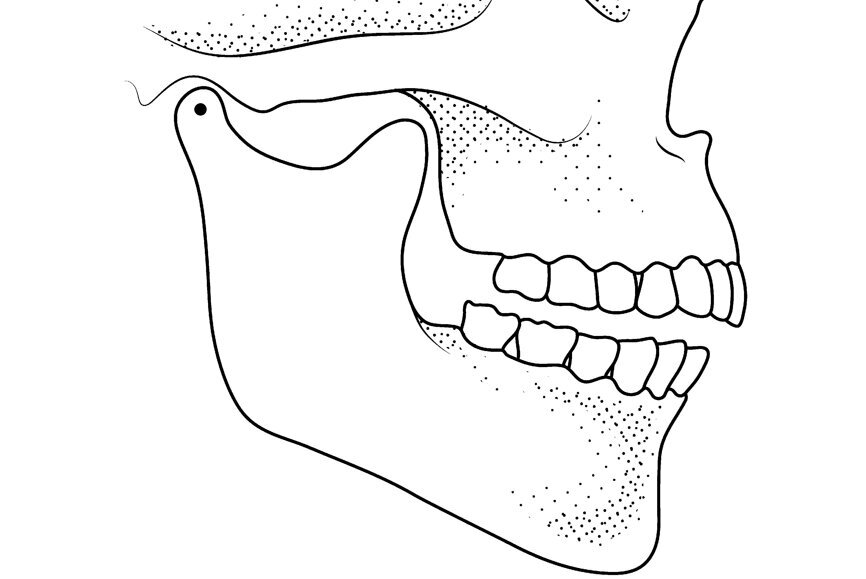

Let us analyse the MP concept further. Three non-collinear points, that is, that are not on the same straight line, can define the position in space of any solid object (Fig. 3). For increased precision, it is advantageous to select points as far apart as possible. The two condyles (first and second points) and the incisal point (third point) can define the position in space of the mandible relative to the anatomical structure of the maxilla/articular eminences (Fig. 4). The position of the condyles on the articular eminences can be defined as condylar position (CP). One stable CP, which is widely accepted, is CR. The position of the mandibular incisal point relative to the maxilla can be defined as the vertical dimension of occlusion (VDO). Using a mathematical formula: MP = CP + VDO. Therefore, the occlusion formula becomes (Fig. 5): occlusion = CP + VDO + IC.

Fig. 3: A drawing of the mandible, anterior teeth and fossae, showing a reversed tripod.

Fig. 4: Mandibular position defined as condylar position and vertical dimension of occlusion.